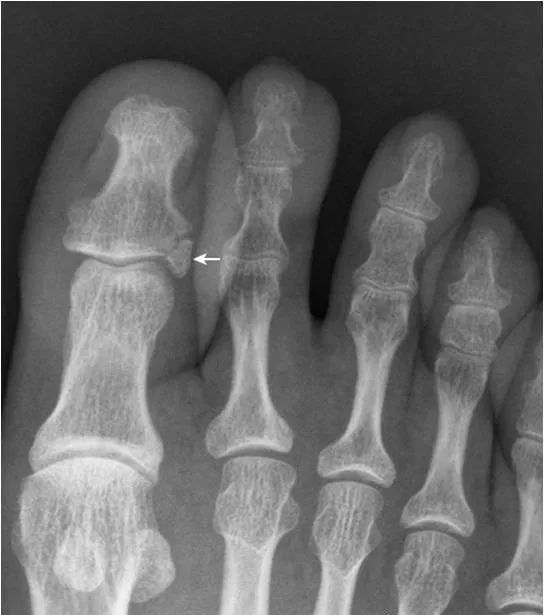

32.拇趾撕脱骨折:

该例为陈旧性撕脱骨折。拇趾外侧基底部部分撕脱,虽游离骨片(箭)边缘清晰,但与基底部有很好的对合,可与关节旁骨相鉴别。